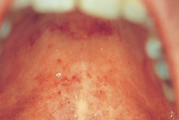

Harilik vill-lööve

Lame lihhen

Punetised

Infektsioosne mononukleoos (suudlemisnakkus), Epstein-Barri viirus (EBV)

Herpangiin

Herpes simplex

Erythema multiforme

Stevens-Johnsoni sündroom

Kontaktist tekitatud kahjustused suulimaskestal